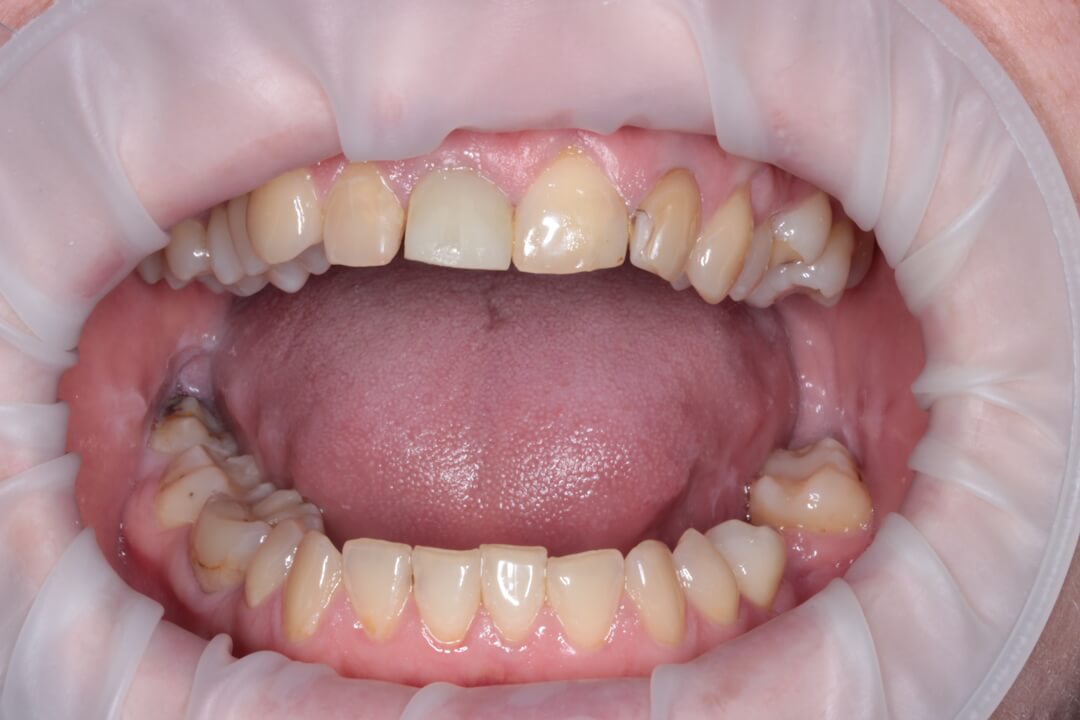

Пациентка в возрасте 49 лет обратилась в клинику для консультации. Ее интересовала возможность улучшить эстетический вид передней группы зубов верхней челюсти. У нее 11-ый зуб был травмирован около 20 лет тому назад. В результате на рентгенограмме диагностирован перелом корня и этот зуб не подлежал повторному восстановлению.

Рис.5 Вид пациентки через 3 месяца после одномоментной имплантации.

В данном клиническом случае показано, что сочетание одномоментной имплантации, немедленного протезирования и хирургической реконструкции твердых и мягких тканей альвеолярного отростка способствует высококачественному восстановлению зубодесневой области в переднем отделе зубного ряда. Положительный результат лечения наблюдается даже при чрезвычайно неблагоприятных начальных условиях для имплантации и зубопротезирования.